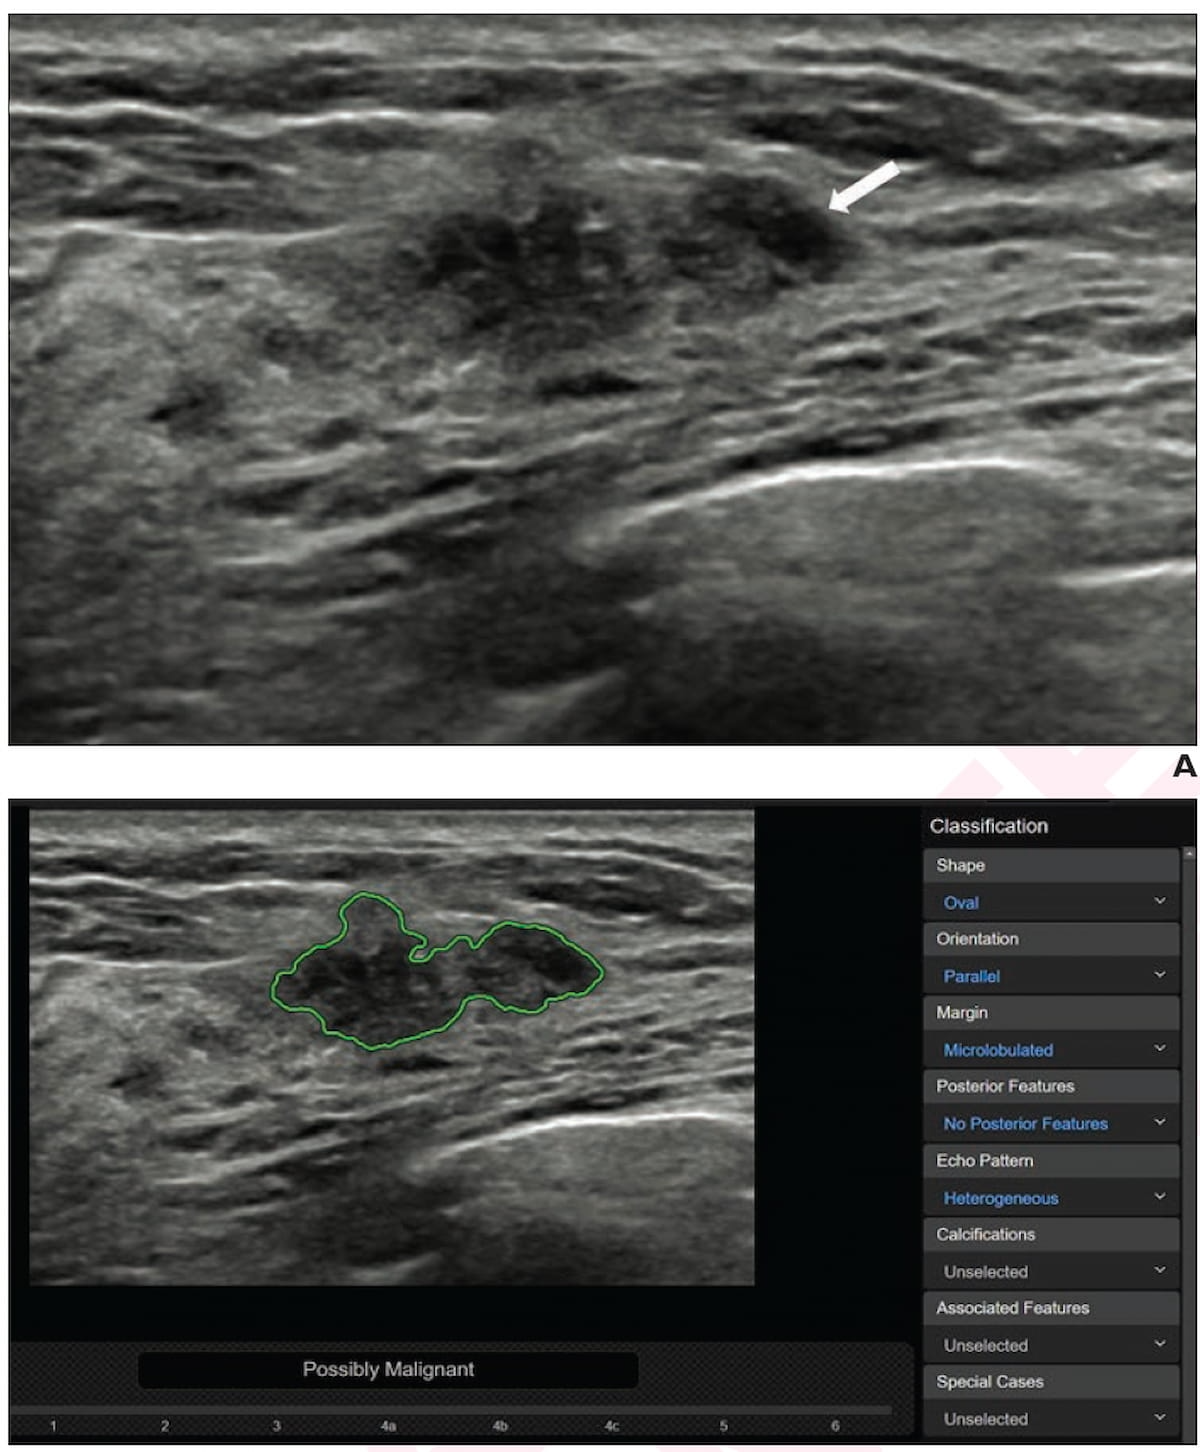

A mass detected with supplemental ultrasound was categorized as a BI-RADS 4B lesion (A) but adjunctive use of the AI software S-Detect noted a possible malignancy. Subsequent surgical pathology showed the mass was invasive ductal carcinoma. (Images courtesy of the American Journal of Roentgenology.)